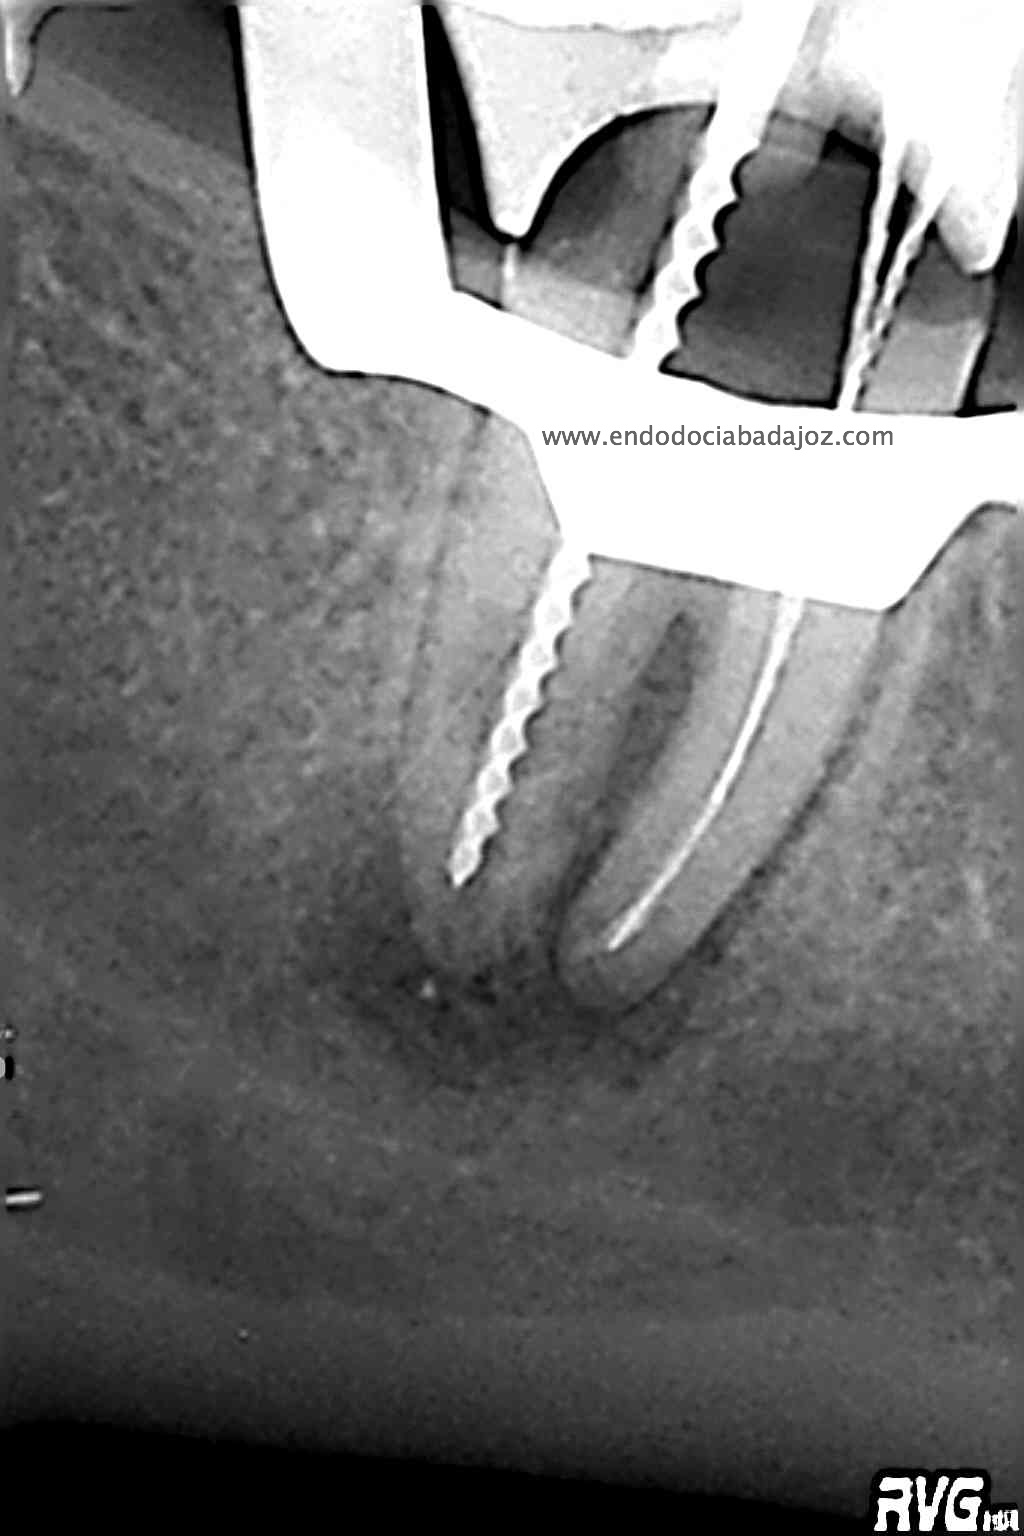

Hemos llamado a revisión a la paciente en varias ocasiones ( 6 meses y 9 meses)

(revision a los 6 meses) (revisión a los 9 meses)

Como podemos observar, la lesión periapical ha regenarado:

Muy buen caso doctor realmente lo felicito . Pero parece ser de el doctor restaurador no hizo un buen trabajo. Se ve en la radiografia de que hay un margen abierto en distal y aparentemente se olvido de poner un poste en el canal distal.